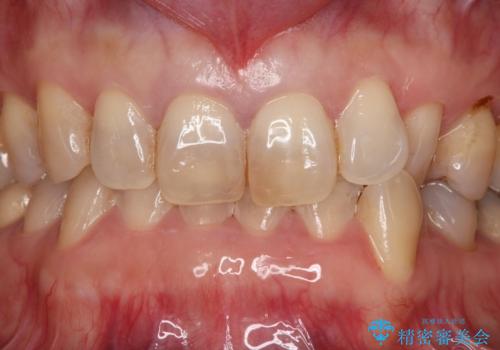

- 前歯の色が年々変わっていき、見た目が気になるので綺麗な歯にしたいと思い当院へ来院されました。

保険ですでに治療がされており、経年劣化が見られ内部にはう蝕もあったため除去し、オールセラミッククラウンにて治療いたしました。